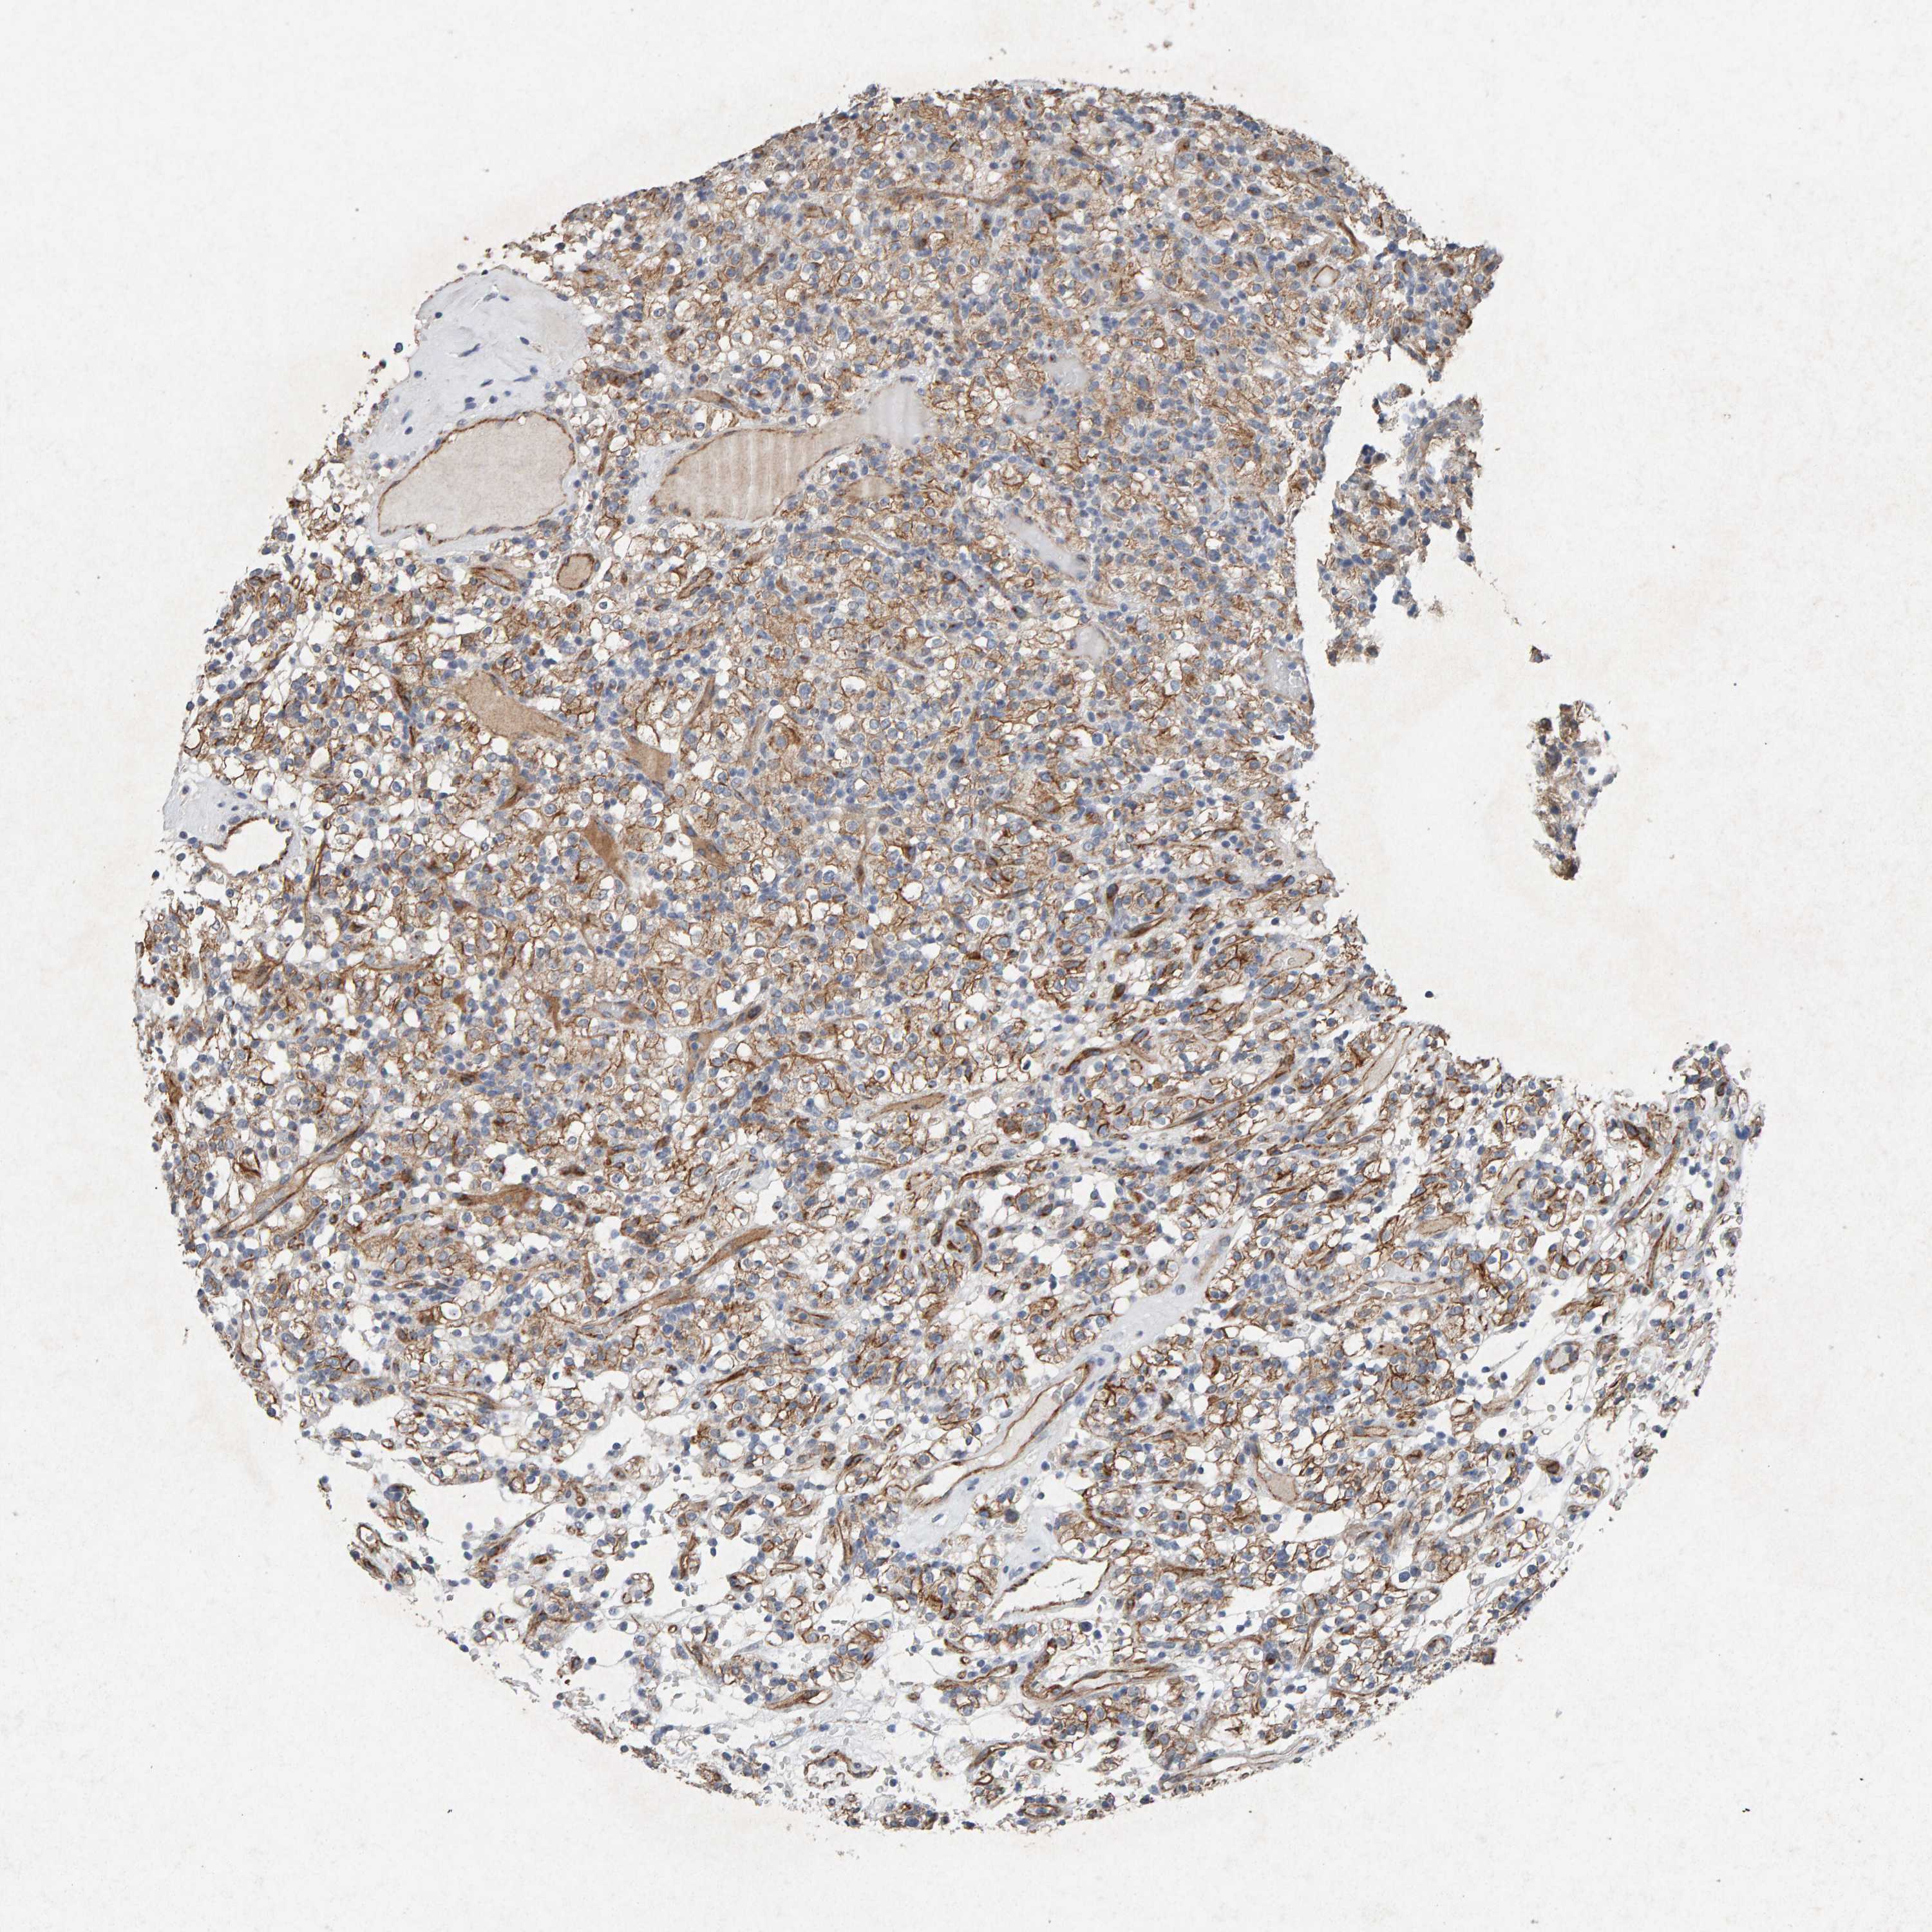

KIDNEY RENAL CLEAR CELL CARCINOMA (VALIDATION) - Interactive survival scatter ploti

The Survival Scatter plot shows the clinical status (i.e. dead or alive) for all individuals in the patient cohort, based on the same data that underlies the corresponding Kaplan-Meier plots. Patients that are alive at last time for follow-up are shown in blue and patients who have died during the study are shown in red.

The x-axis shows the expression levels (FPKM) of the investigated gene in the tumor tissue at the time of diagnosis. The y-axis shows the follow-up time after diagnosis (years). Both axes are complimented with kernel density curves demonstrating the data density over the axes. The top density plot shows the expression levels (FPKM) distribution among dead (red) and alive patients (blue). The right density plot shows the data density of the survived years of dead patients with high and low expression levels respectively, stratified using the cutoff indicated by the vertical dashed line through the Survival Scatter plot. This cutoff is automatically defined based on the FPKM cutoff that minimizes the p-score. The cutoff can be changed by dragging the vertical line or by entering a cutoff value in the square labeled "Current cut-off".

Under the Survival Scatter plot the p-score landscape (black curve; left axis) is shown together with dead median separation (red curve; right axis). Dead median separation is the difference in median mRNA expression between patients who have died with high and low expression, respectively. It is calculated as follows: median FPKM expression of dead patients with high expression - median FPKM expression of dead patients with low expression. This is intended to aid the user in visually exploring custom cutoffs and the associated p-scores and dead median separation.

Individual patient data is displayed and can be filtered by clicking on one or more of the category buttons on the top of the page. Categories describing expression level and patient information include: high, low, alive, dead, female, male and tumor stages. The scale of the x-axis can be toggled between linear and log-scale by clicking on the "x log" button. Mouse-over function shows TCGA ID, patient information and mRNA expression (FPKM) for each patient.

& Survival analysisi

Kaplan-Meier plots summarize results from analysis of correlation between mRNA expression level and patient survival. Patients were divided based on level of expression into one of the two groups "low" (under cut off) or "high" (over cut off). X-axis shows time for survival (years) and y-axis shows the probability of survival, where 1.0 corresponds to 100 percent.

PTPRM is validated prognostic, high expression is favorable in Kidney Renal Clear Cell Carcinoma (validation)

Best expression cut offi

Based on the FPKM value of each gene, patients were classified into two groups and association between prognosis (survival) and gene expression (FPKM) was examined. The best expression cut-off refers the FPKM value that yields maximal difference with regard to survival between the two groups at the lowest log-rank P-value. Best expression cut-off was selected based on survival analysis .

When clicking on this number, the vertical dashed line indicating cut-off, the interactive survival plot, and the Kaplan-Meier curve will be adjusted to show results based on the best expression cut-off.

: 78.72

TCGA RNA samplesi

RNA-seq data is reported as average FPKM (number Fragments Per Kilobase of exon per Million reads), generated by the The Cancer Genome Atlas (TCGA) .

Normal distribution across the dataset is visualized with box plots, shown as median and 25th and 75th percentiles. Points are displayed as outliers if they are above or below 1.5 times the interquartile range. FPKM values of the individual samples are presented next to the box plot.

Average pTPM 78.8

Number of samples 100